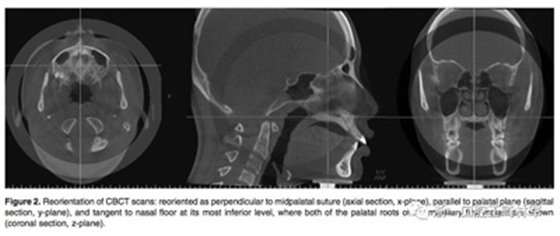

在治療前(T1)和擴弓后3個月(T2)拍攝CBCT,獲得的數據由In Vivo Dental(Anatomage,San Jose,Calif)分析。為了在T1和T2階段設置相同的參考平面,CBCT圖像沿著腭中縫(x平面)定向,平行于腭平面(y平面)并且與鼻底(z平面)相切(Figure 2)。在腭中縫處評估橫向骨骼擴張,并在三個不同的平面進行線性測量:鼻底,硬腭和硬腭以下5mm。在根尖和牙冠水平測量橫向牙齒擴張(Figure 3)。評估兩側的牙槽傾斜度,牙長軸,牙齒垂直高度和骨開裂等情況(Figure 4,5)。所有測量均在每個上頜前磨牙和磨牙區(qū)域進行。